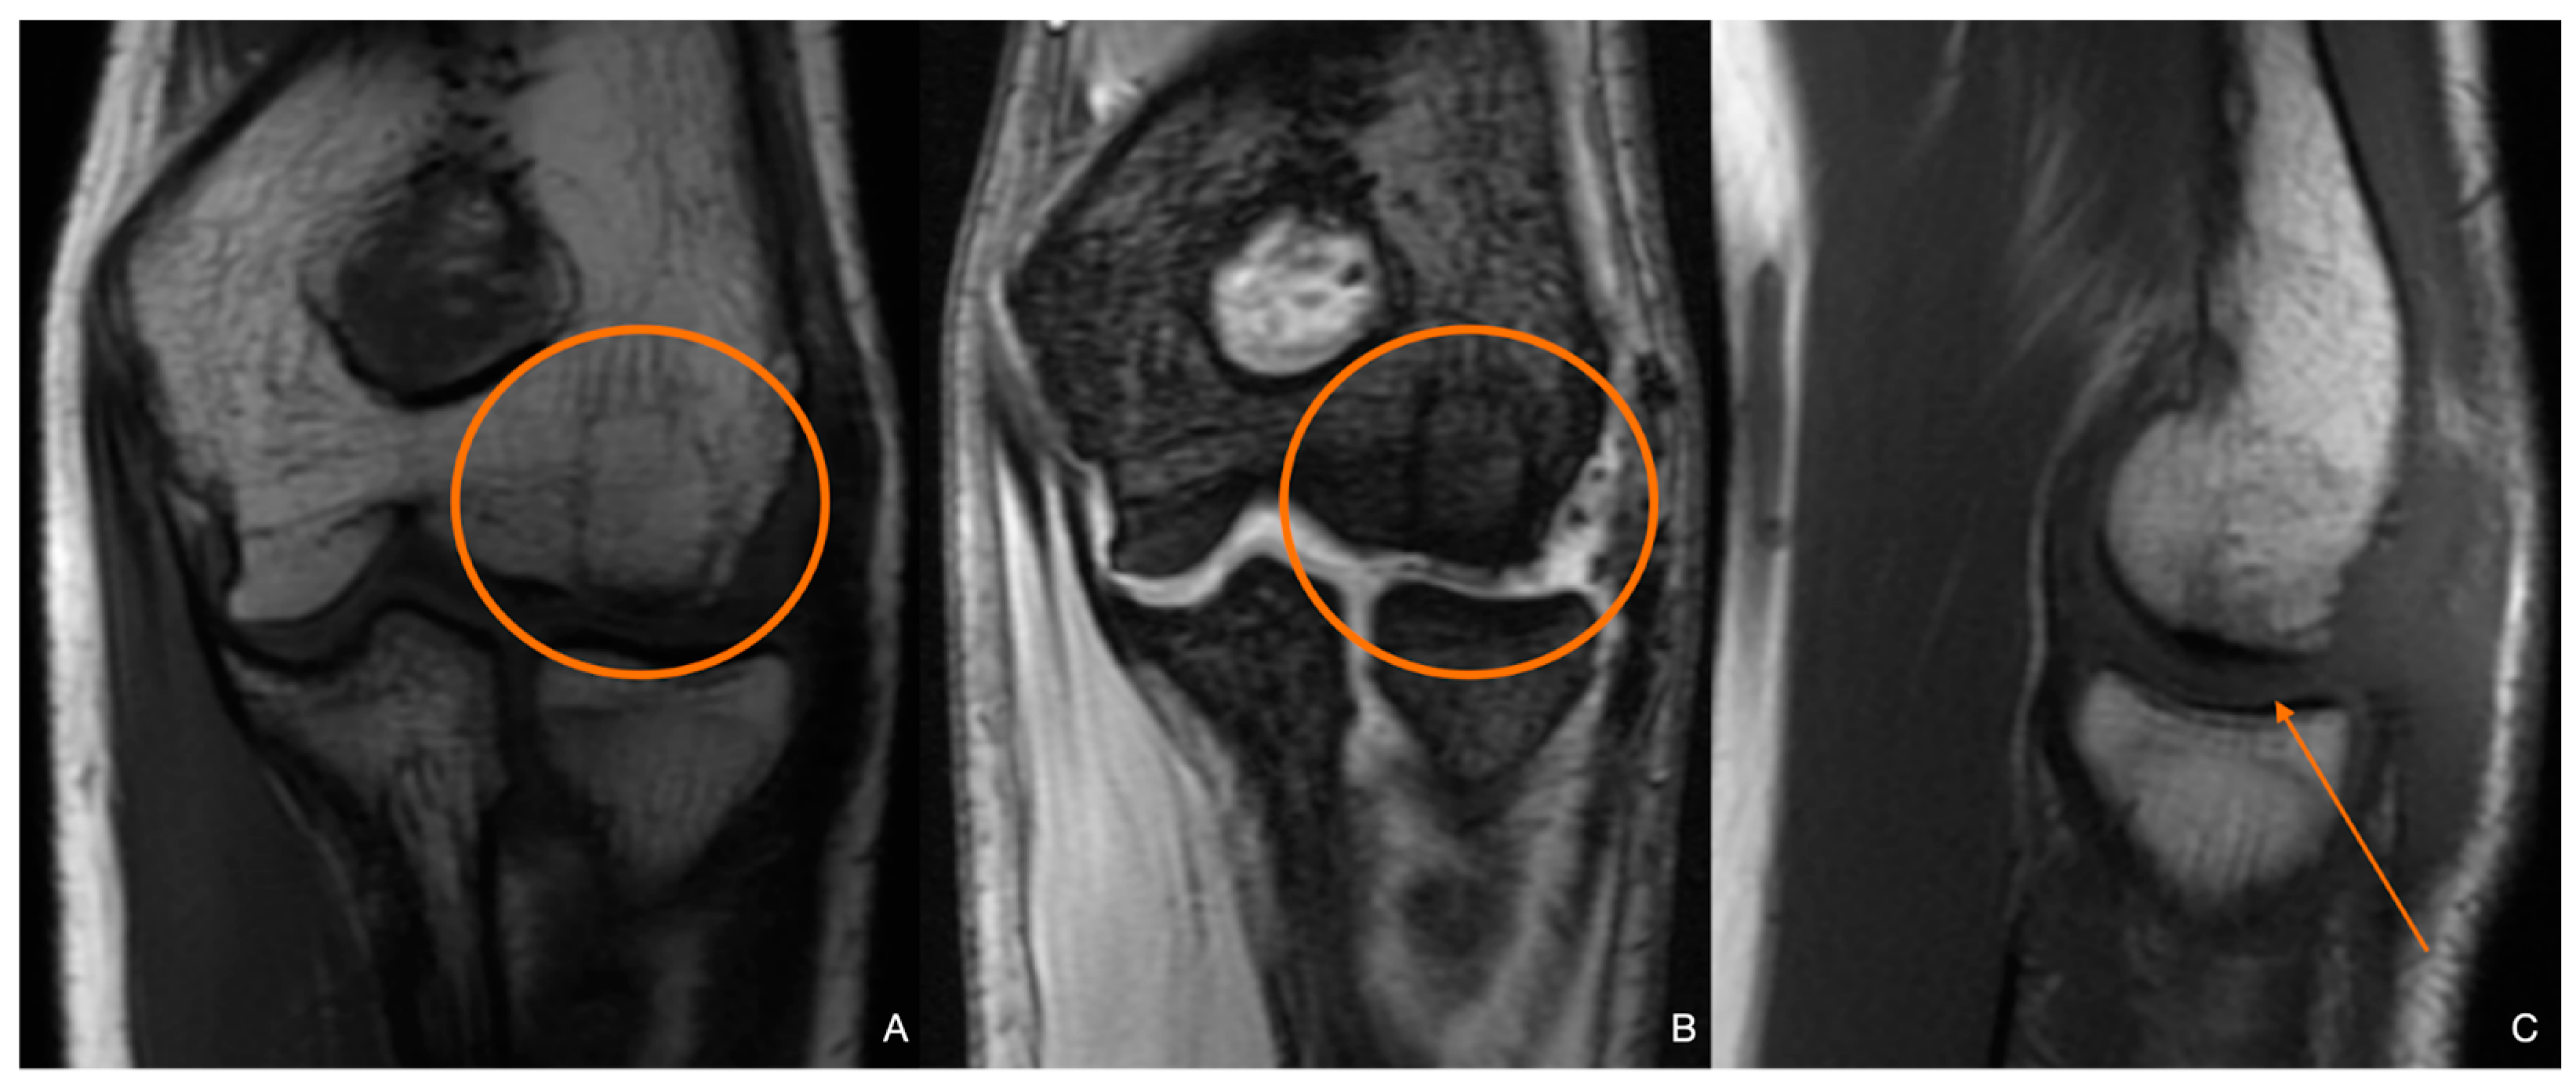

| Stage 1 | Small subchondral compression | Intact Lesion | A stable lesion of the softened area covered by intact cartilage | Thickening of articular cartilage and low signal changes | Small change in signal, without clear fragment margins | Epiphyseal cartilage lesion with necrotic center |

| Stage 2 | Partially detached osteochondral fragment | A lesion with signs of early separation | Lesions with partial discontinuity which are stable when probed | Articular cartilage is breached, with a low signal rim behind the fragment indicating fibrous attachment | Osteochondral fragment with clear margins, without fluid in between | Epiphyseal cartilage lesion with complete or incomplete rim calcification |

| Stage 3 | Completely detached, non-displaced | Partially detached lesion | Lesions with complete discontinuity which are not dislocated (Dead in situ) | High signal changes behind the fragment indicate synovial fluid between the fragment and the underlying subchondral bone | Fluid is partially visible between the fragment and bone | Partially or completely ossified lesion |

| Stage 4 | Completely detached and displaced—loose body | Craters with loose bodies (salvageable or non-salvageable) | Empty defect bed with loose or dislocated fragment | Loose body | Fluid surrounds the fragment but it is still in situ | Healed osseous lesion with scar |